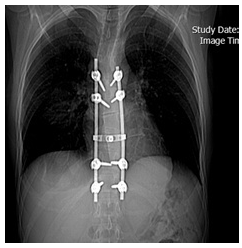

The cyst cavity was irrigated with hypertonic saline solution. After All the cysts element were extirpated, exploration of spinal canal was performed by the neurosurgeons, and the cystic mass eroded the vertebral pedicle, body, vertebral corpus destruction, transverses process and spinal column. The patient underwent T7 to T8 partial laminectomy, T7 vertebral body resection, curettage of lesion and removed of all hydatid elements, necrotic tissue and Partial resection of the six ribs. During exploration of spinal Colum, Multiple pearly white cysts were found in the extradural space compressing the dural sac, all cyst elements was removed and released spinal cord. The operative field was soaked with hydrogen peroxide for a few minutes and then washed with normal saline. Posterior pedicle screw fixation was performed to stabilize the thoracic spine (Figure 7).

Figure 7: Pedicle screw fixation.